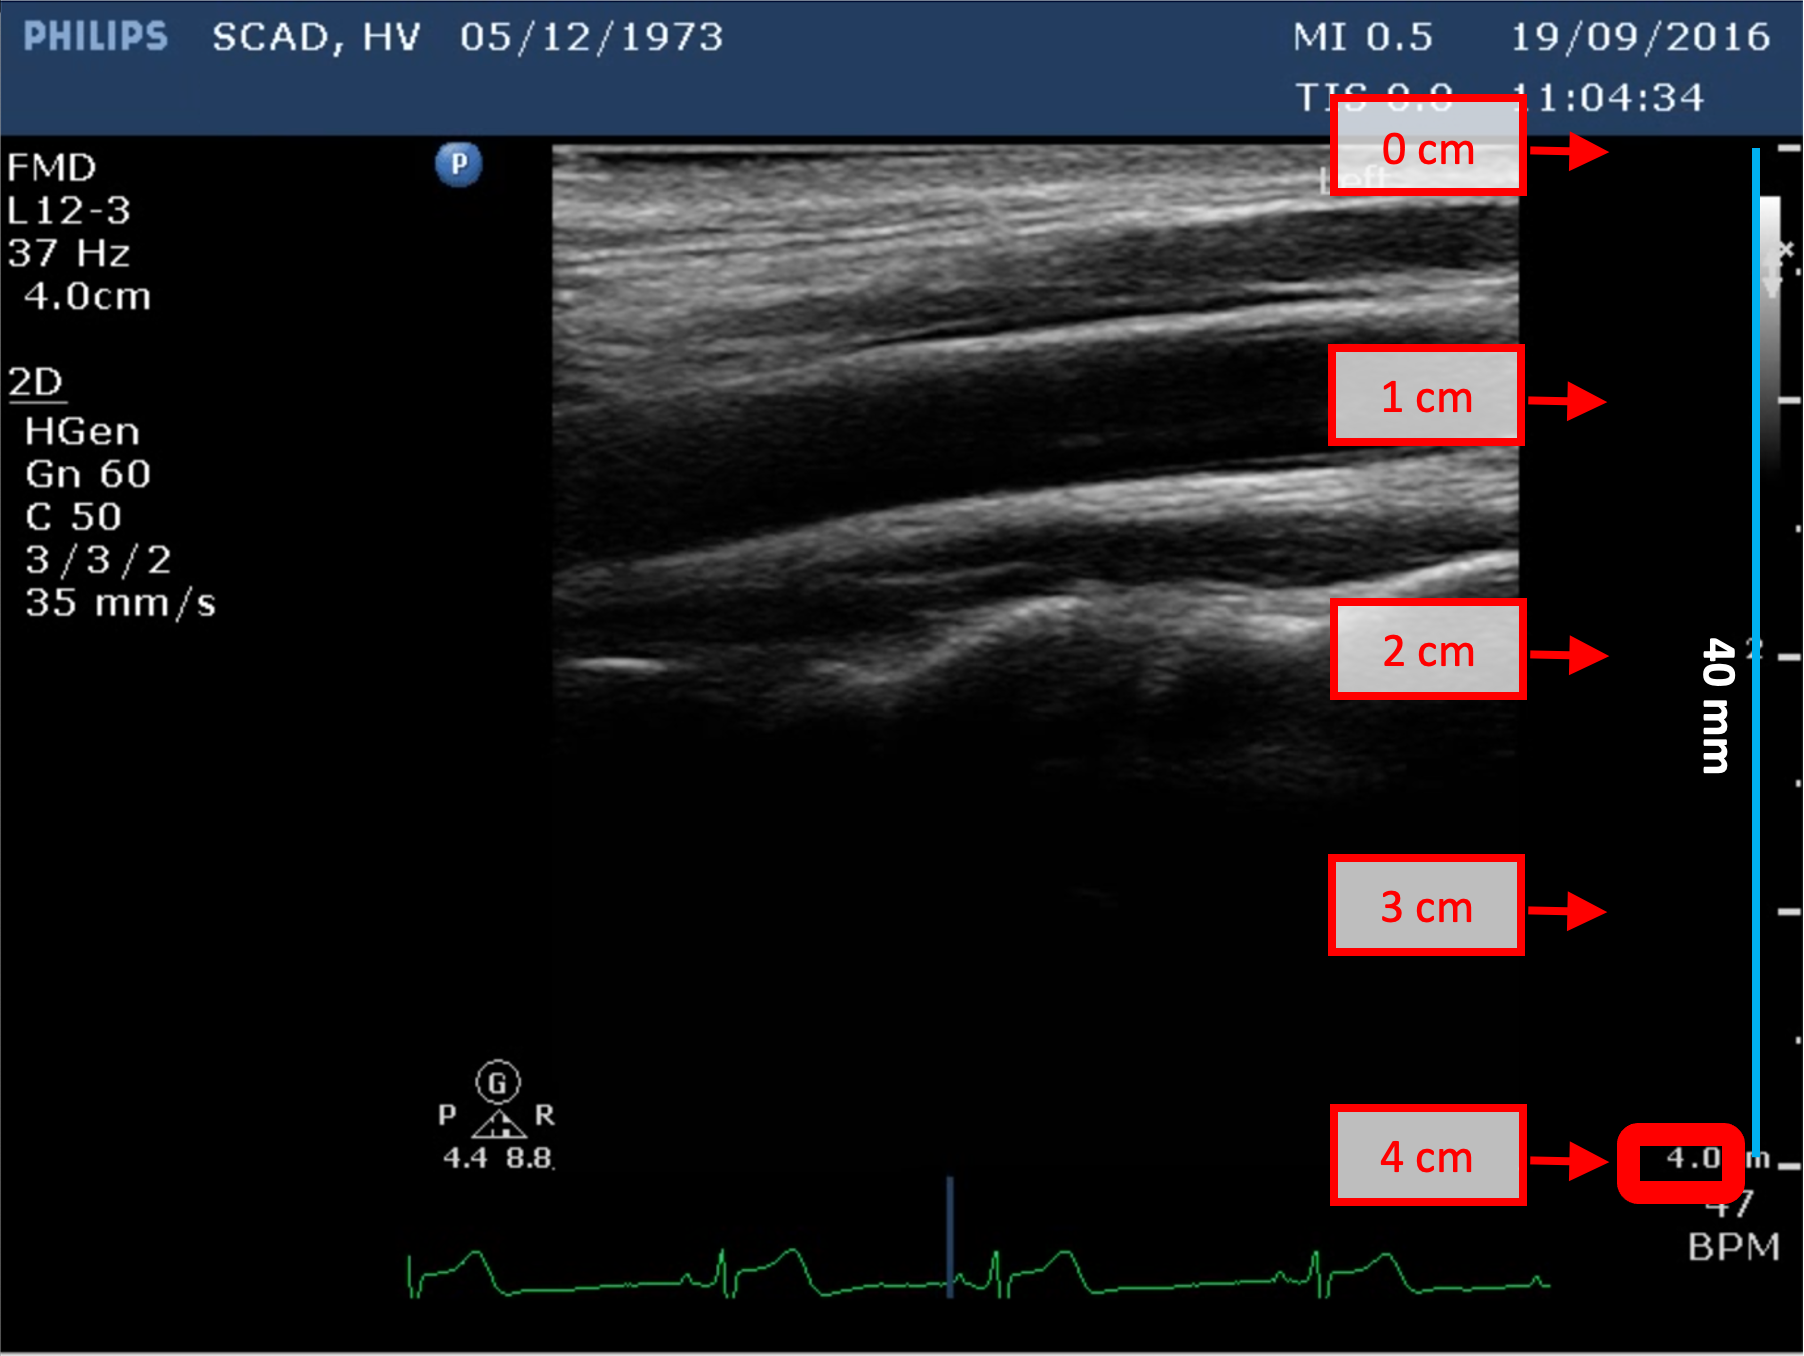

Exemples d'étalonnage en mode B

Les images suivantes présentent des exemples d'étalonnage de l'image en mode B. Les éléments graphiques en rouge indiquent où trouver les informations relatives à la profondeur de l'image échographique.